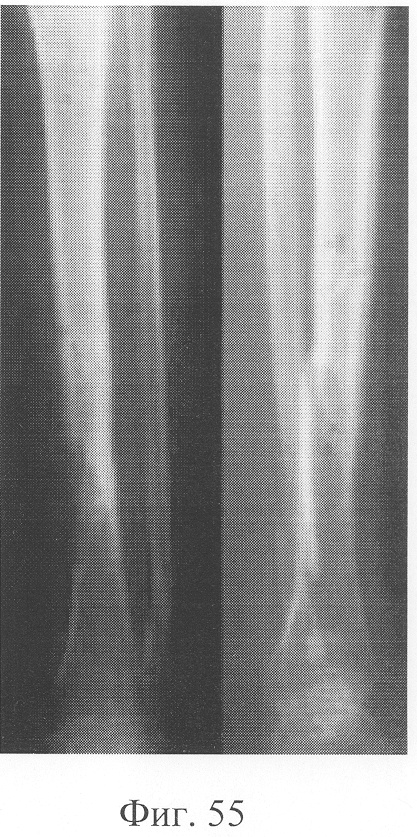

Больной П., 46 лет, поступил для планового оперативного лечения с диагнозом «ложный сустав левой большеберцовой кости» (фиг.47-49 – клинические и рентгенологические данные до операции). В анамнезе открытый перелом обеих костей голени, по поводу которого после проведения первичной хирургической обработки раны был наложен аппарат внешней фиксации с одномоментной репозицией. В связи с замедленной консолидацией проводилась микрокомпрессия и микродистракция, что не имело четкого положительного эффекта. Через 11 месяцев после травмы отмечалась выраженная патологическая подвижность при клинической пробе, рентгенологически отмечены признаки формирования ложного сустава. Аппарат внешней фиксации был демонтирован, и после заживления ран выполнена операция: экономная резекция костных фрагментов, фиксация в аппарате, костная пластика деминерализованным костным трансплантатом, заселенным аутологичными мезенхимальными стволовыми клетками по предложенной методике. В послеоперационном периоде дренажи удалены на 2-е сутки, швы сняты на 14 сутки, с 5-х суток разрешена ходьба при помощи костылей, с 7-х суток нагрузка на оперированную конечность (фиг.50-52 – клинические и рентгенологические данные в процессе лечения). Аппарат внешней фиксации демонтирован через 3 месяца при клинико-рентгенологической картине сращения (фиг.53-55 – результат лечения).